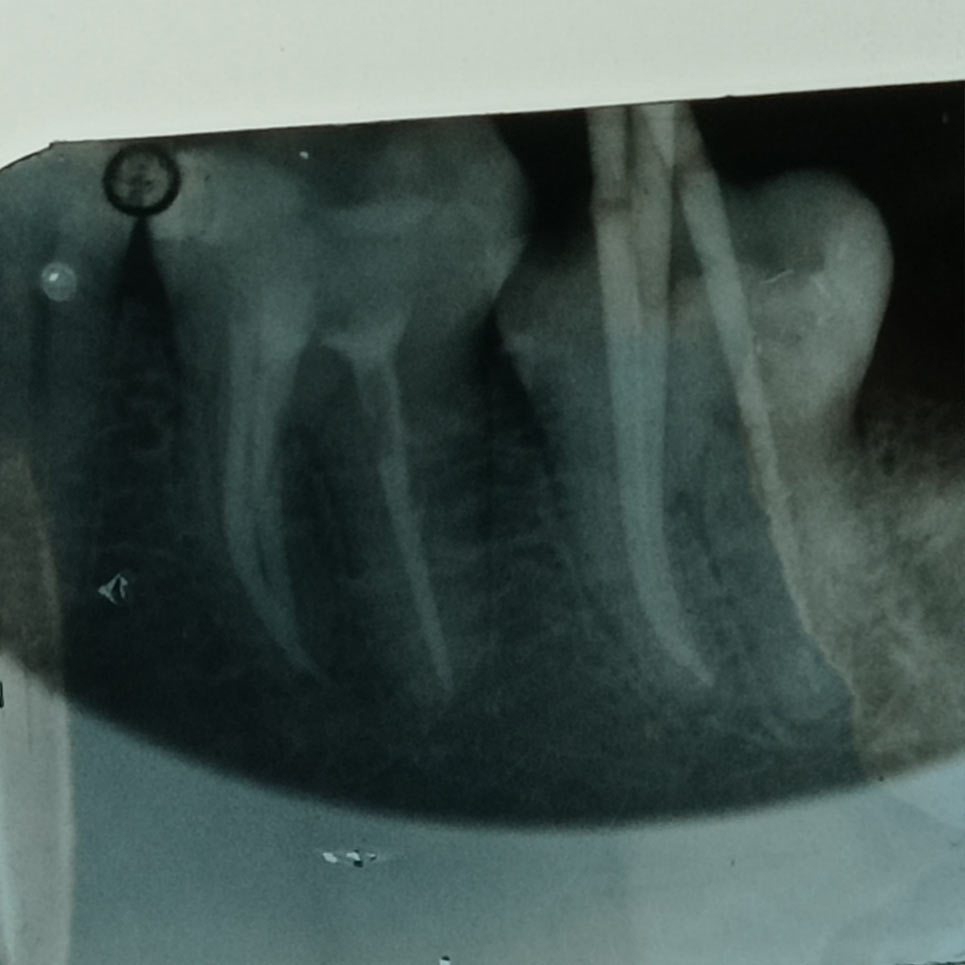

Η απονεύρωση, γίνεται όταν πλέον το δόντι έχει νεκρωθεί για κάποιο λόγο, βλέπε φλεγμονή, κάταγμα, εκτεταμένη τερηδόνα, είτε γιατί έχει σπάσει αρκετά και πρέπει στα πλαίσια της αναπλήρωσης του και αποκατάστασης να απονευρωθεί για να διατηρηθεί σωστά στο στόμα μας, είτε γιατί έχει κάποια κύστη.

Είμαστε εξειδικευμένοι ~ με ετήσια μετεκπαίδευση στον τομέα των απονευρώσεων ~ και πραγματοποιούμε τις θεραπείες μας, με όλα τα τελευταία μέσα και τεχνολογία, πλήρως εναρμονισμένοι, ενημερωμένοι, για το μέγιστο άρτιο αποτέλεσμα.

Απονεύρωση, χωρίς να σπάσουν τα νεύρα σας! ~ Άμεσα, ακίνδυνα, αποτελεσματικά.